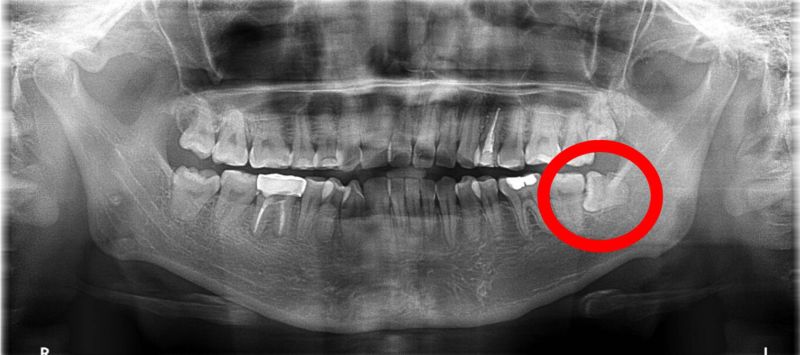

30歲的大明牙痛數日,左臉腫脹延伸到頸部就醫,臨床及X光檢查發現感染源來自左下水平智齒(紅圈處)導致蜂窩性組織炎。 圖片來源:蔡承熹醫師提供